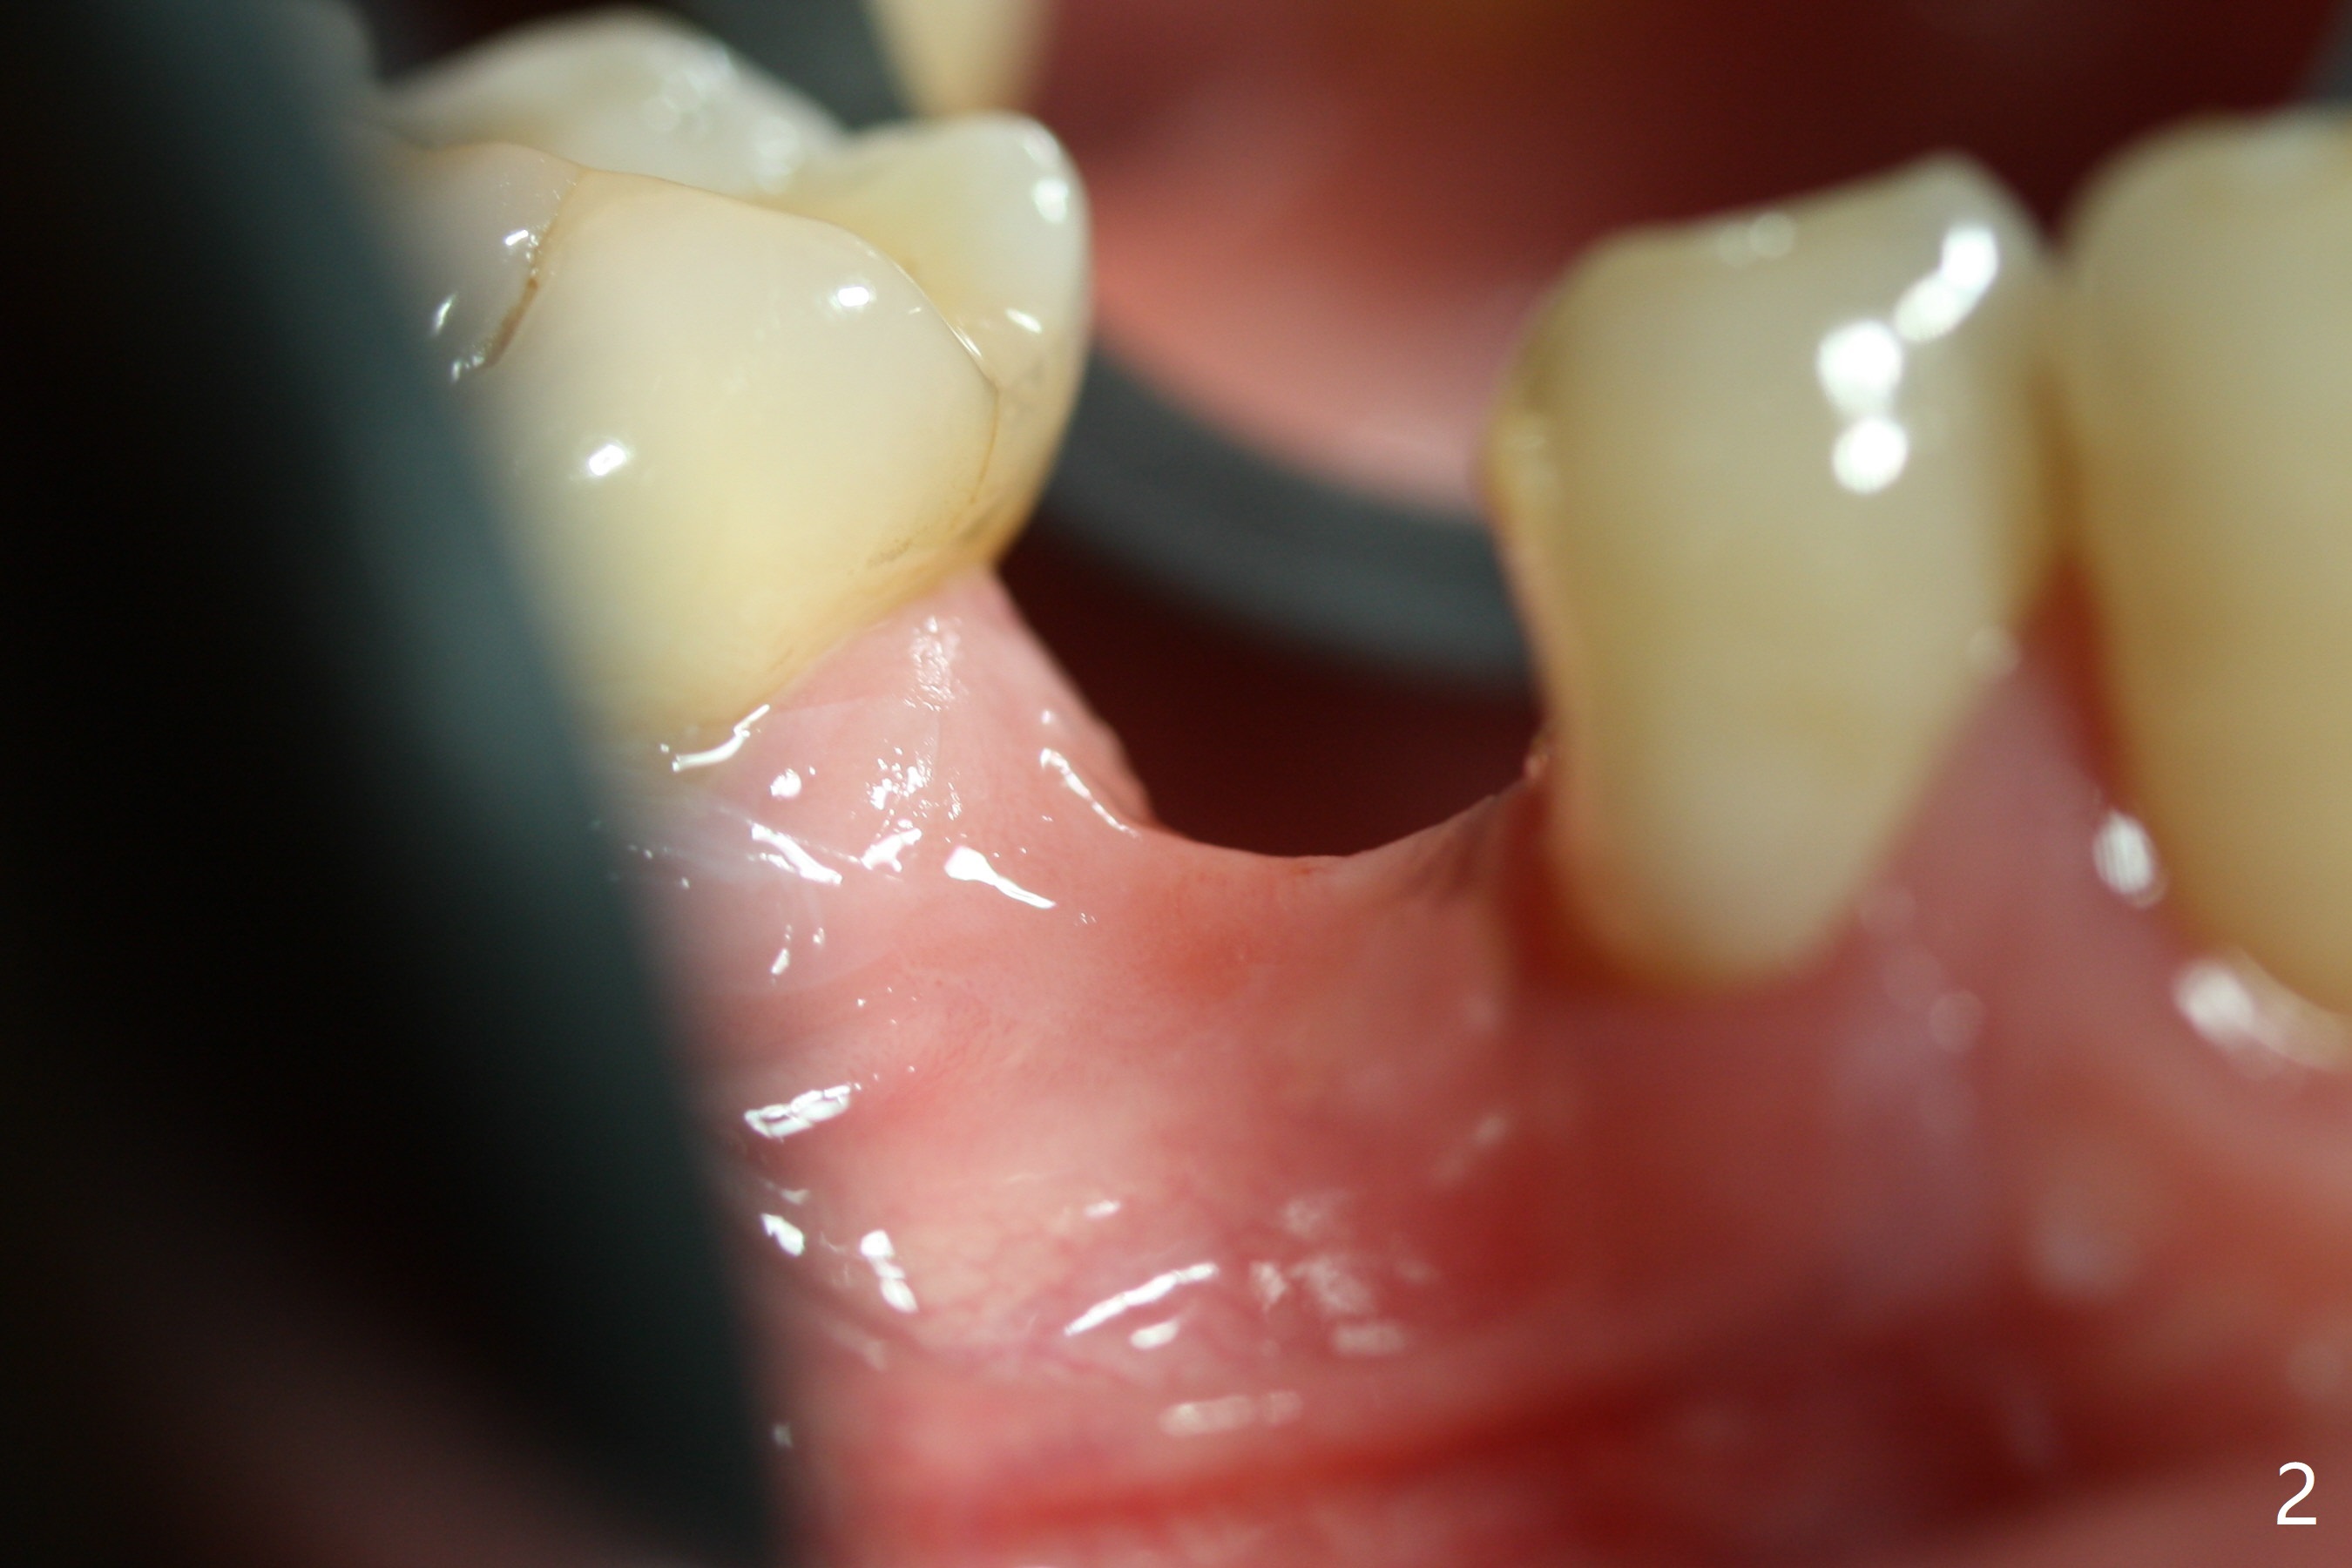

The base of the edentulous ridge at #29 looks wide (Fig.1), but the most coronal portion is the thin soft tissue (Fig.2). It appears that there has been bone resorption since extraction. The initial osteotomy depth is 11.5 mm (Fig.3). Since the Mental Loop seems to be nearby, the depth of subsequent osteotomy (3 mm) remains the same (Fig.4). Although the final depth of osteotomy is 13 mm, the implant placed is short (3.8x11.5 mm, Fig.5,6), as compared to the immediate implant (3.8x18 mm) at the contralateral side (#20). There is mild bone resorption mesially 4 months postop (Fig.7). The crown is loose (poor osteotomy position, guide necessity) 7 months post cementation immediately prior to 18 cementation, although there is no gross bone losss 1 year 7 months post cementation (Fig.8).